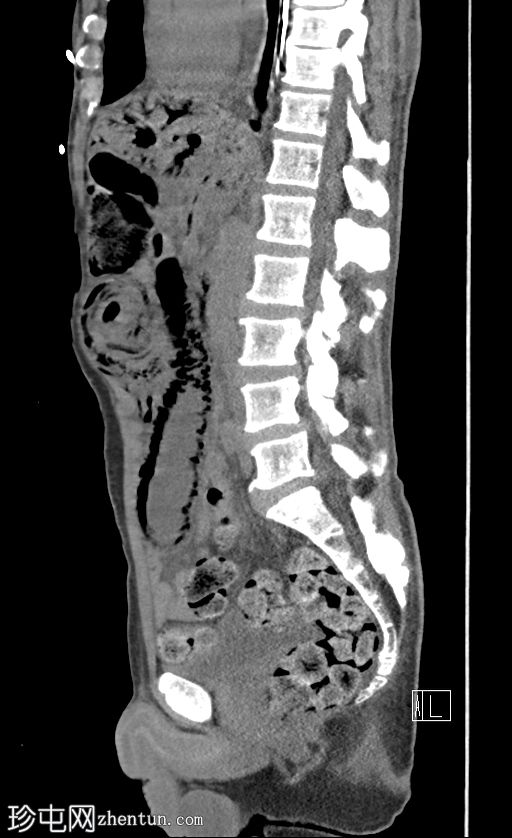

矢状位片

平扫

门静脉积气。胃管末端位于胃底。下腹部可见长段小肠套叠,套叠起始点位于右下腹。伴有远端小肠广泛积气,左下腹肠段扩张,最符合小肠梗阻和缺血的表现,可能由长段小肠套叠引起。